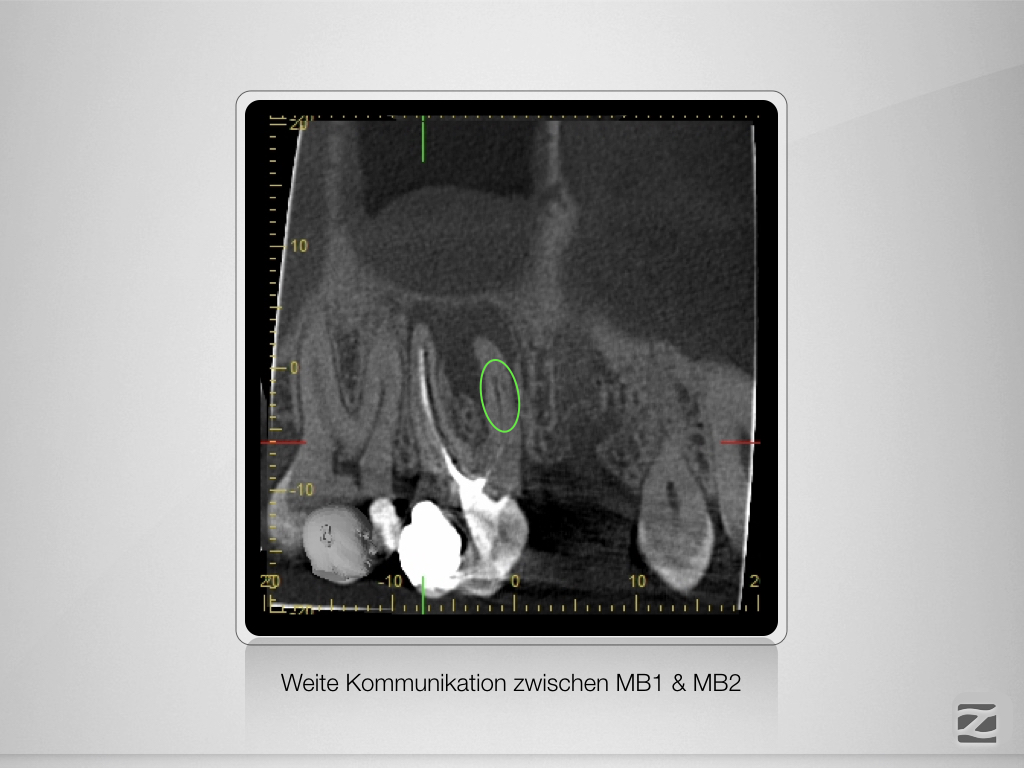

16D.006

Späte Erkenntnis